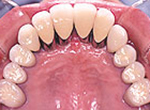

上顎前歯のインプラント